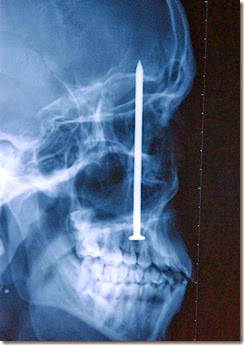

http://lh5.ggpht.com/-2WtgemFiPUk/U0FNFm8NknI/AAAAAAAAhcw/vC1TyYj_t38/nail_thumb1.jpg?imgmax=800 Seorang pria mengeluh sakit gigi dan ketika diperiksa oleh dokter giginya, ia menemukan hasil mencengangkan. Ada sebuah paku tertancap di dalam kepala pria ini. Ternyata dia tanpa sengaja tertembak o